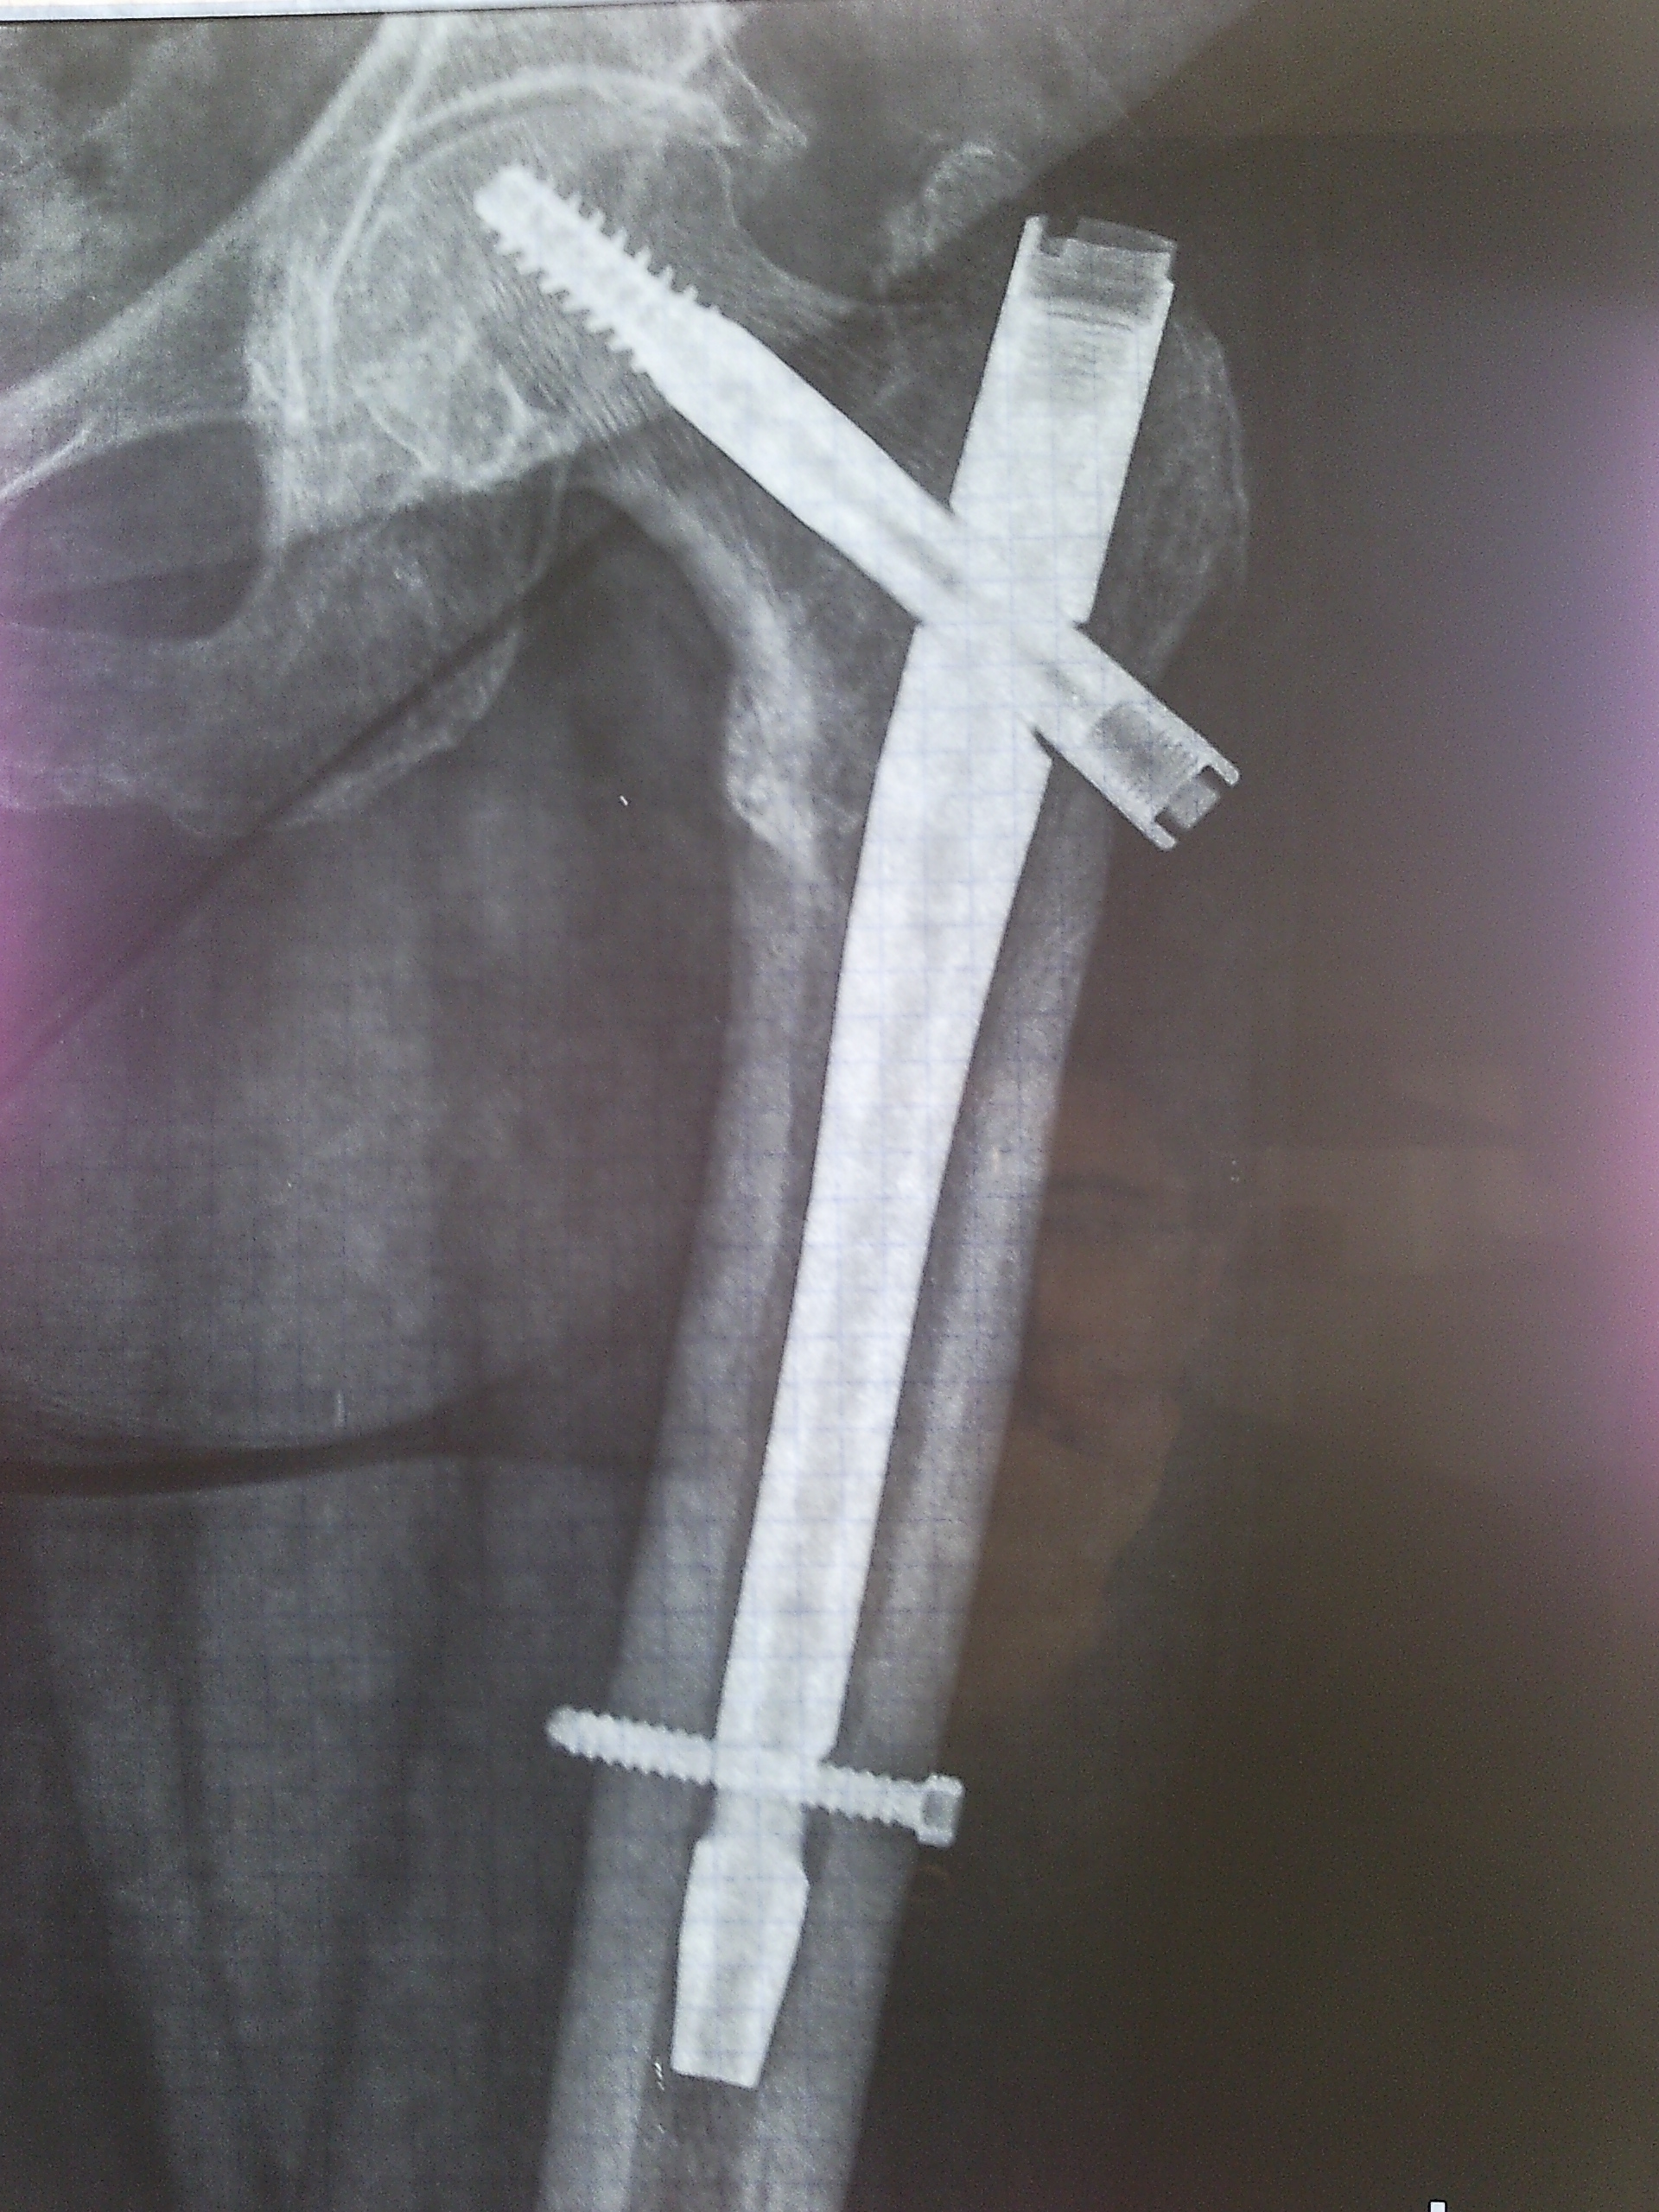

Ενδομυελική Ήλωση

Η ενδομυελική ήλωση είναι η χειρουργική τεχνική συγκράτησης της ανάταξης καταγμάτων μακρών οστών με τη χρήση ενός καρφιού (ήλου) που τοποθετείται μέσα στον αυλό του οστού (ενδομυελικά). Η καταγματική εστία δεν ανοίγεται χειρουργικά και η ανάταξη επιτυγχάνεται με έμμεσο τρόπο.

Η τεχνική αυτή είναι ελάχιστα παρεμβατική, δεν διαταράσει τη βιολογία των μαλακών μορίων γύρω από το κάταγμα και επιτρέπει τη γρήγορη λειτουργική αποκατάσταση του ασθενούς.